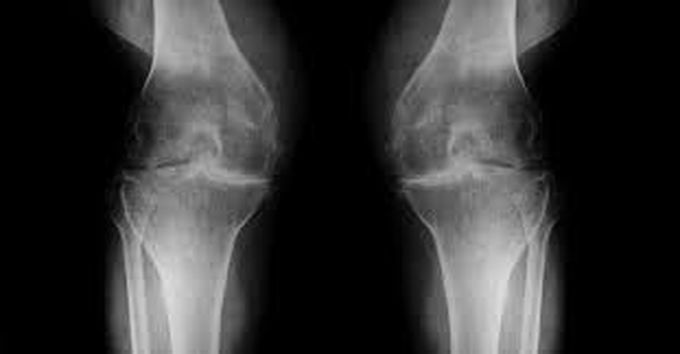

Arthritis is managed best initially by a physical medicine and rehabilitation (PM&R) physician who is highly trained in the conservative treatment of joint and muscle problems. Treatment methods used include weight loss, acetaminophen, NSAIDs, corticosteroid injections, viscosupplementation and rehabilitation. Viscosupplementation has recently become more common as it helps to alleviate arthritis pain through injection of a gel-like substance that mimics the natural lubricant created in the joint to allow more “cushion” within the joint. If pain is still persistent regardless of conservative management, a referral from a PM&R physician to an orthopedic surgeon may be necessary to consider total joint arthroplasty.